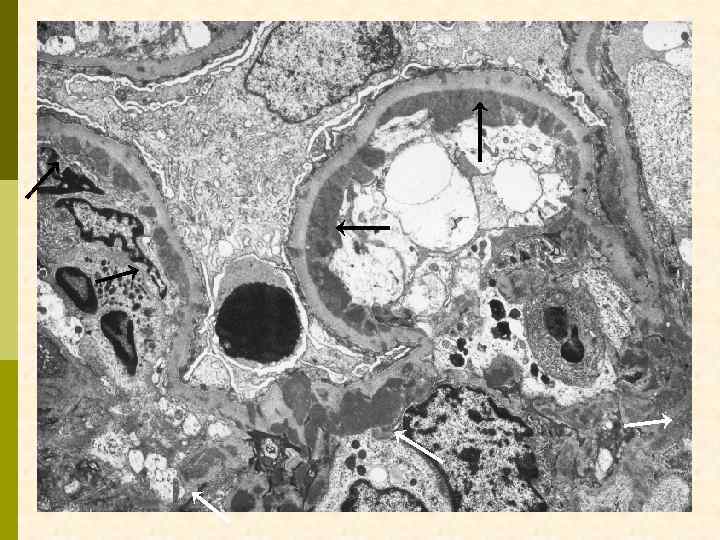

* * C Ядро эндотелиоцита C

Эритроцит МПГН, III тип. Грубые изменения ГБМ, резкое утолщение, лакуны, истончение плотной пластины, субэпителиальные депозиты